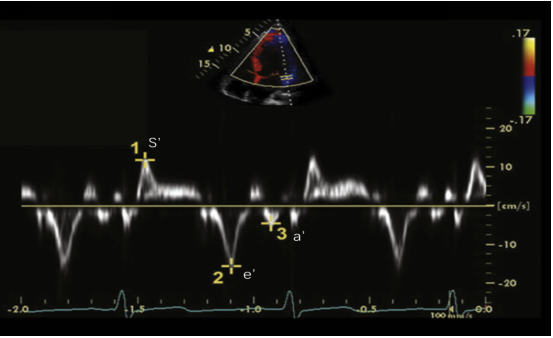

(3)组织多普勒(TDI)和TDI测量的三尖瓣环运动:我们一般选择脉冲波组织多普勒(TDI)在右室基底段游离壁来测量。其参考图像如图16所示。

图片

图16. RV-TDI的测量

典型的TDI包括三个波:顶点向上的收缩波(Sm)(S’),远离顶点的早期舒张波(Em)(E’)和晚期舒张波(Am)(A’),收缩波Sm前的等容收缩IVC。Sm(S’)的参考值常规大于11 cm/s,若小于10 cm/s,则代表收缩功能的明显下降。Sm和Em之间有等容舒张期,Am和Sm之间有等容收缩期。

(5)组织多普勒(LV-TDI):心尖四腔心切面,在二尖瓣瓣环处或侧壁处,取样容积5~10 mm进行测量。典型的LV-TDI图像如图25所示。

图25. LV-TDI的测量

收缩期的Sa(s’)峰,舒张早期Ea(e’)峰和舒张晚期Aa(a’)峰。Ea(e’)反映心肌的松弛能力,在侧壁测量的数值高于室间隔壁测量的值,其正常参考值为大于10 cm/s(侧壁)和8 cm/s(室间隔);一般来说,Aa(a’)大于8 cm/s。